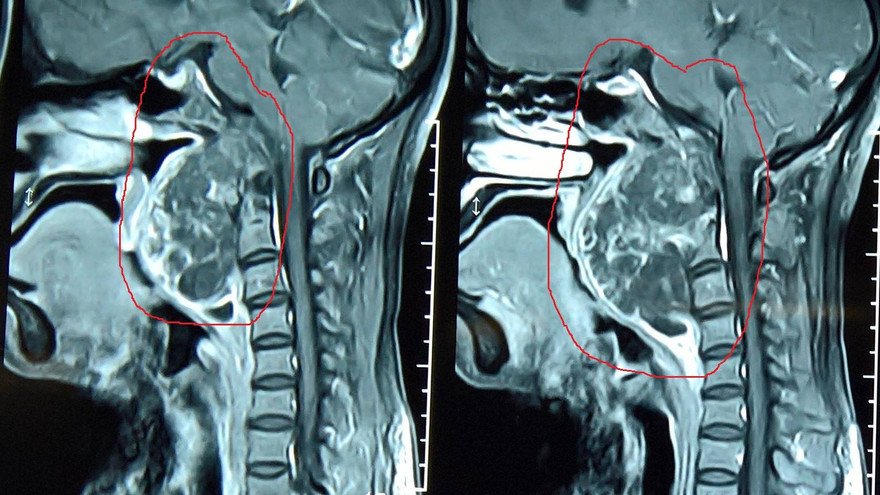

Cũng theo PGS. Kỳ, u nguyên sống là một loại ung thư xương được tìm thấy trong hộp sọ và cột sống. U hay bị nhầm với u amidan hoặc u bên họng. Tỷ lệ để mắc loại ung thư này là 1/ 1 triệu người.

U nguyên sống phát triển từ tàn tích rất nhỏ của sụn khớp và có thể người bệnh đã mang nó từ trong bụng mẹ. Bởi vì rất hiếm, nên u nguyên sống ít được nghiên cứu, nhưng các chuyên gia có thể loại bỏ nguyên nhân di truyền khỏi loại ung thư này.